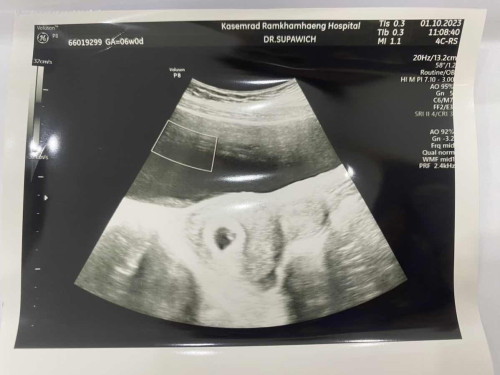

ทัอง 6 W ค่ะ

เจอแต่ถุงตั้งครรภ์คะ